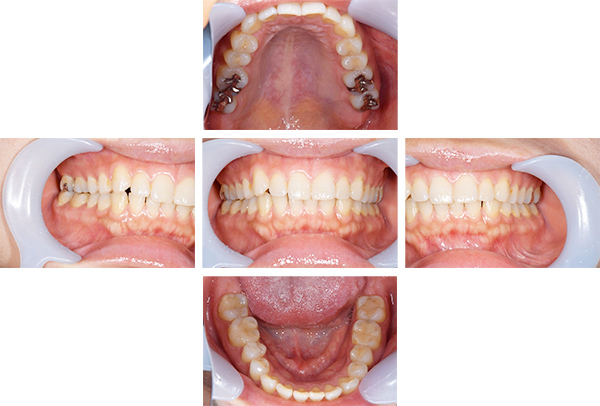

歯列矯正・インレー・クラウン症例

前歯が黒っぽいのが気になる、

悪いところは全部治したい

年齢 54代女性

主訴 歯をきれいにしたい

症例写真(治療前)

担当医師所見

治療前:

八重歯が目立ちます。また銀歯もおおく、見た目が気になります。虫歯も散見できます。

レントゲン写真(治療前)

根の治療を3本すでに治療されています。1本根の奥の詰め物が疎になっていますので、根の部分の再治療も行う必要がありそうです。銀歯の中で虫歯になっているものもあります。

治療中

矯正装置をつけています。だんだん八重歯が動いてきているのがわかります。今回のケースでは、抜歯を行わずに矯正ができました。

症例写真(治療後)

治療後:

矯正治療と虫歯の治療すべて終わったときの写真になります。見た目も最初の頃とは全く違いますし、お口の中もすごく綺麗です。

治療

方針

まずは虫歯の治療を行い、被せ物をする部分は仮歯をいれて矯正を行う。矯正終了後、仮歯の部分を最終的な被せ物に変えていく。また気になっていた銀歯もセラミックに変えて終了となった。

内容

セラミックインレー、オールセラミックプレミアム、矯正

特記

事項

虫歯の治療によって歯が一時的に染みるようになる可能性があります。また、歯を抜かずに矯正を行っていますが、全ての方で歯を抜かずに矯正ができるわけではありません。